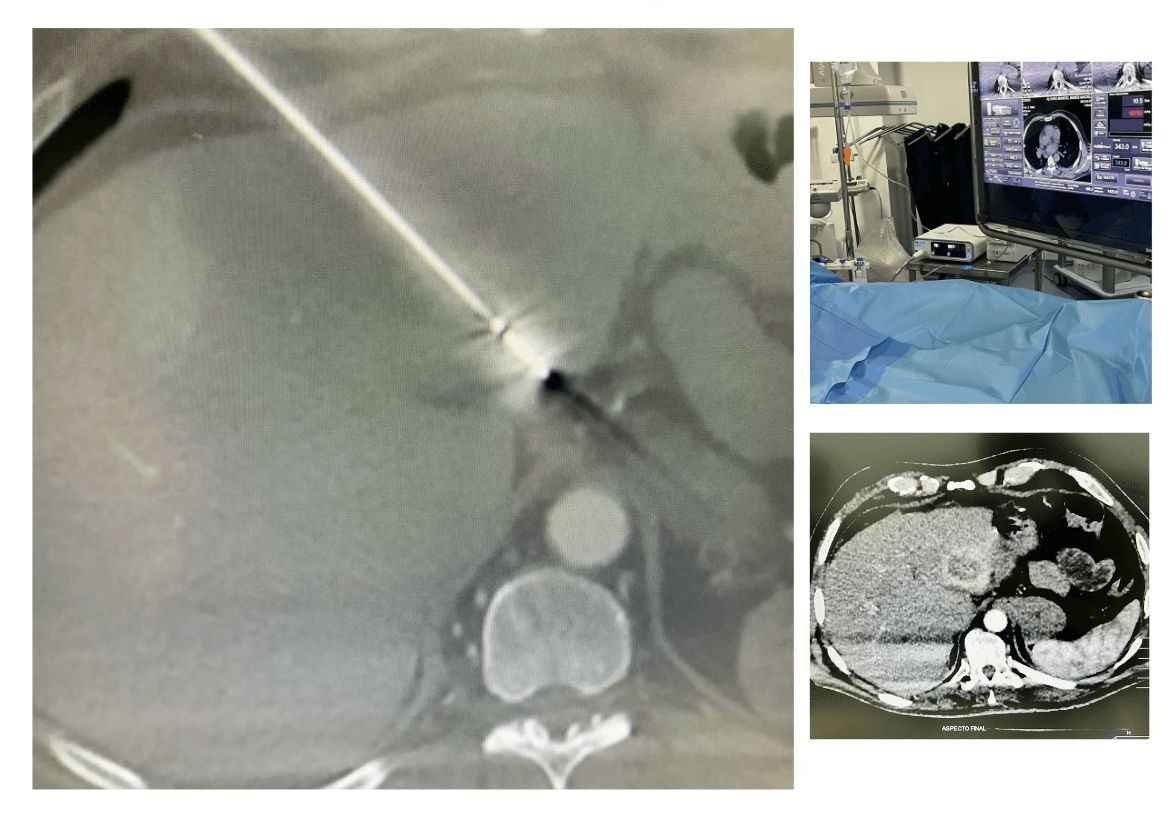

Realizar cirurgias de casos complexos utilizando o Sistema de Ablação Emprint™ já é uma realidade em Recife, desde último dia 07 de abril, quando foi realizada com sucesso no Hospital Real Português, uma cirurgia de ablação por micro-ondas em um paciente, de 68 anos, portador de câncer de fígado.

Conduzida pelo cirurgião intervencionista Gustavo Andrade, o procedimento alcançou os resultados planejados com precisão e consistência. Segundo o especialista “a nova tecnologia permite destruir completamente o tumor com margem de segurança em apenas alguns minutos. Através do aquecimento controlado do tecido com uma agulha posicionada sob orientação por imagem, induzimos a morte do tumor com cura superior a 95% para lesões de até 4 cm. Esta nova tecnologia já é aplicada no fígado, rim, pulmão, ossos e tiroide, estando em teste para mama e outros órgãos”, informou.

O Sistema de Ablação Emprint™ oferece precisão, previsibilidade e confiança ao cirurgião, pois dispõem de controle térmico, de campo e de comprimento de onda, que garantem a formação de zonas de ablação esféricas precisas. Outro importante diferencial do sistema é a redução potencial do tempo e os custos do procedimento, pois o mesmo tem a capacidade de criar zonas de ablação esférica grandes com uma única antena.